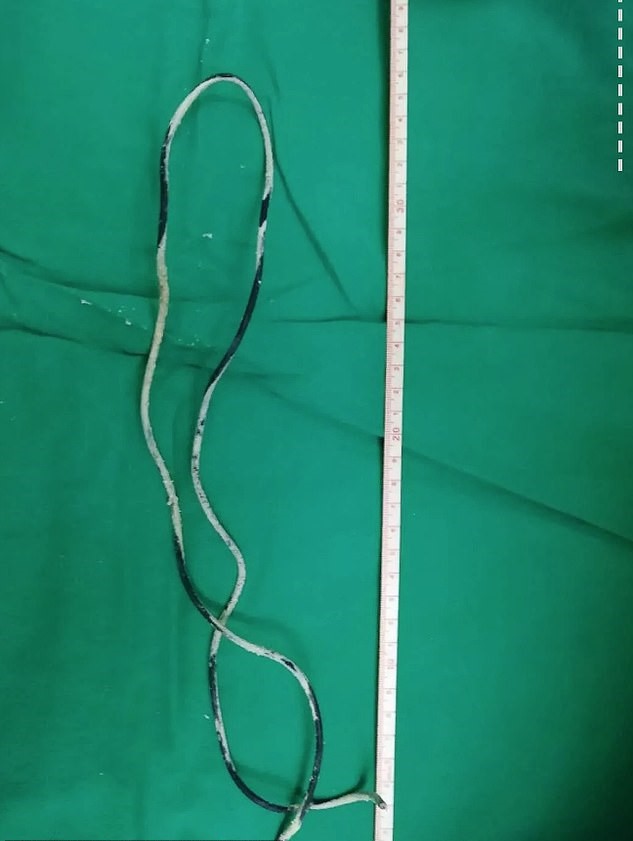

Medics immediately scheduled Xiao He to undergo the surgery and they pulled out the 2ft. long electrical wire from his urethra.

The chief surgeon who led the operation, Dr. Cai Chongyue, said: “I didn’t expect that such a long wire could be inserted through the urethra.

“Fortunately, the wire did not continue to cause damage in the bladder.”